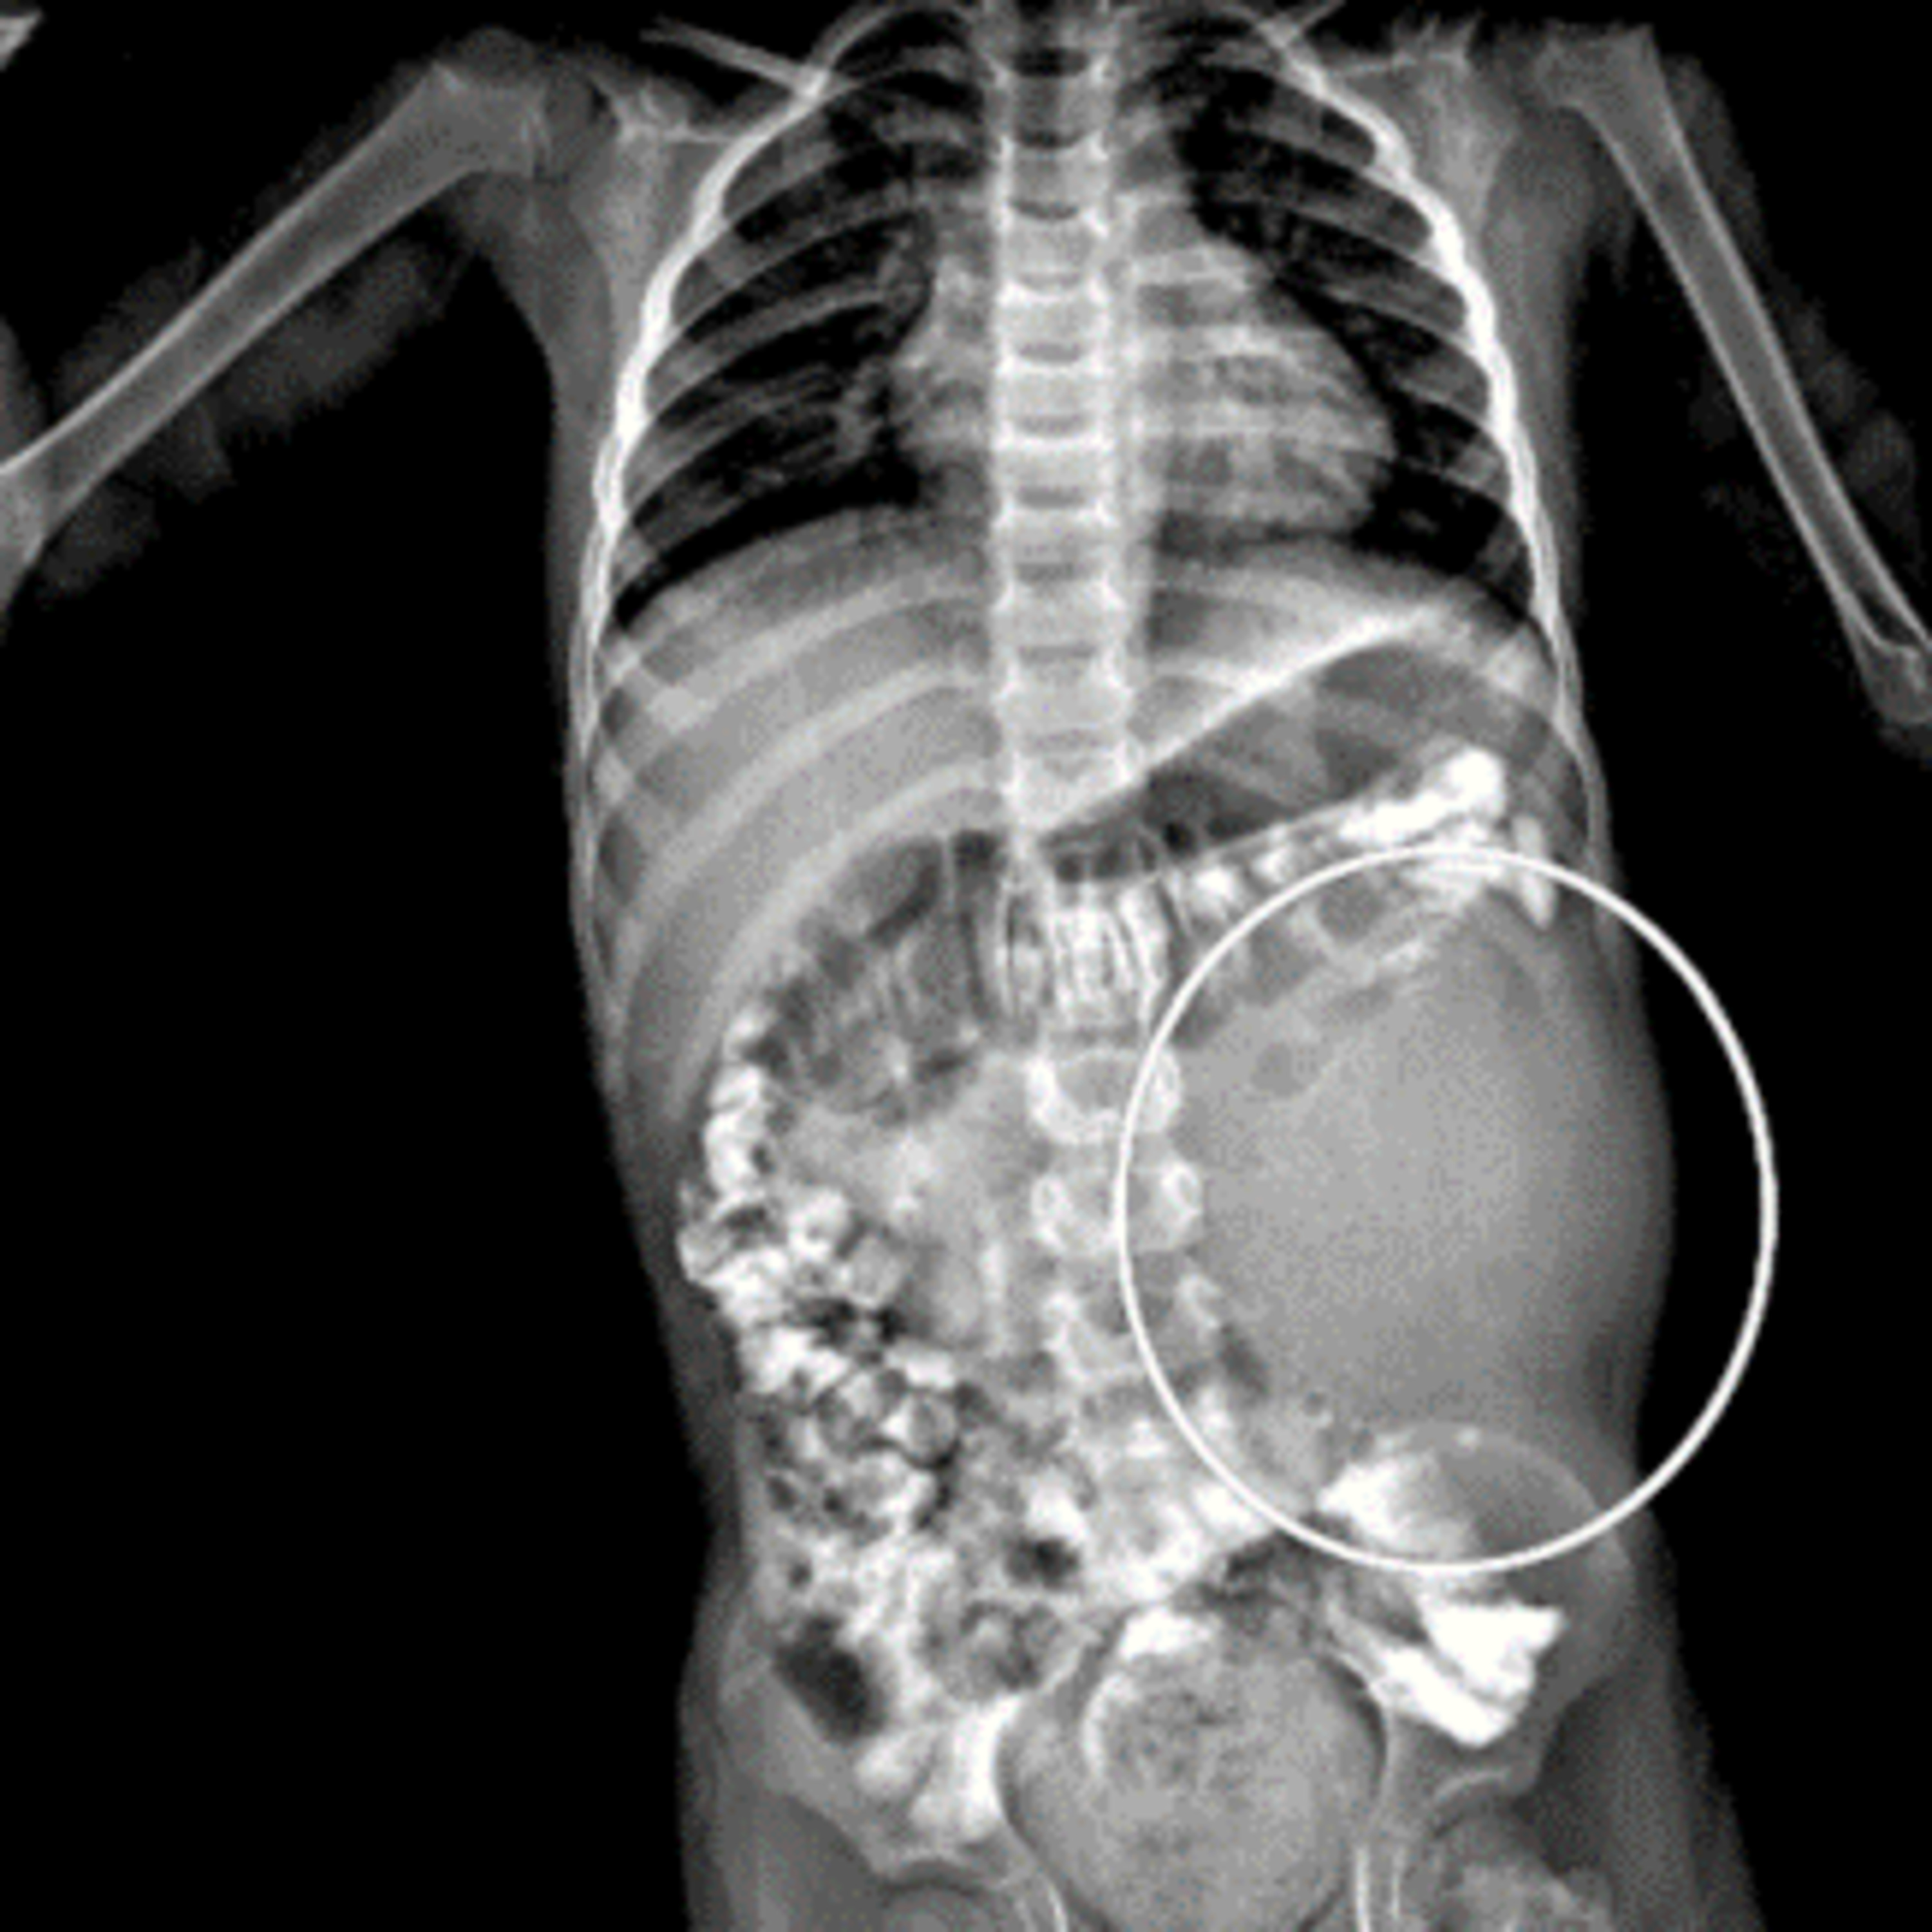

Tema médico: Nefroblastoma o tumor de Wilms

Urología